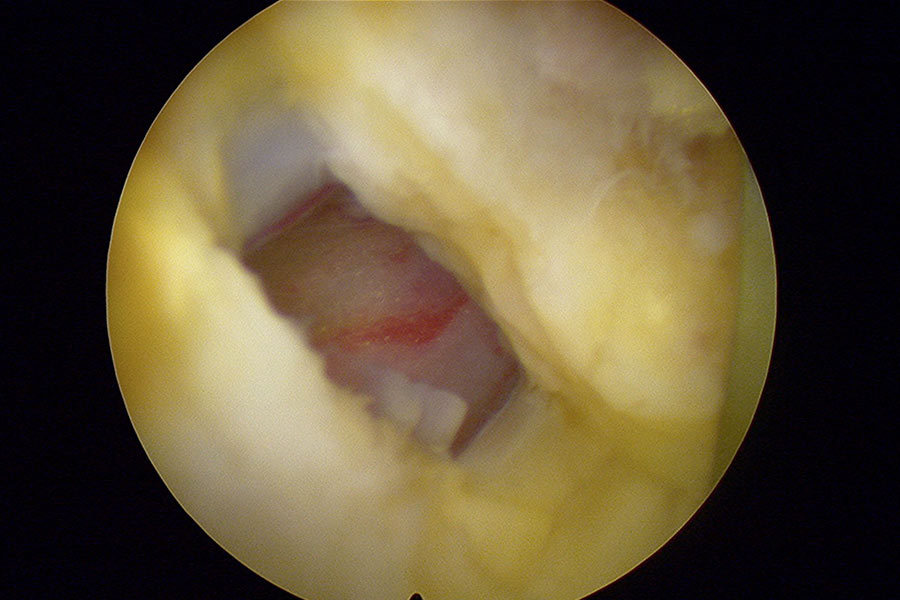

La hernia se eliminará con una técnica de endoscopia mínimamente invasiva, con una incisión de unos 2 mm, es decir, que dejará una cicatriz mínima en el paciente y que garantiza una recuperación mucho más rápida que en el caso de las intervenciones convencionales..

hernia-discal-lateralizada